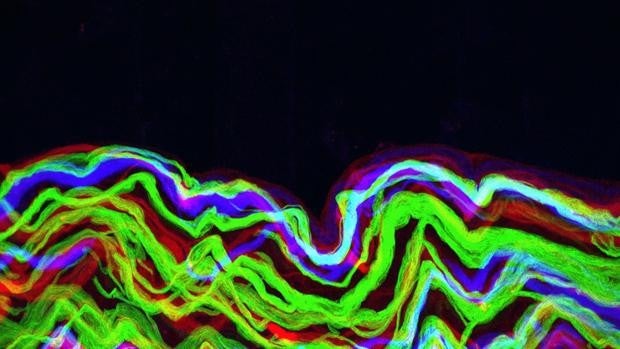

Escuchar la Sonata de Mozart para dos pianos en re mayor (K448) durante al menos 30 segundos puede estar asociado con picos menos frecuentes de actividad eléctrica asociada a la epilepsia en el cerebro en personas con epilepsia resistente a los medicamentos. Los hallazgos, que también sugieren que las respuestas emocionales positivas a K448 pueden contribuir a sus efectos terapéuticos, se publican hoy en Scientific Reports. Estos datos, curiosamente, no resultan sorprendentes, ya que investigaciones anteriores han demostrado que escuchar la Sonata K448 de Mozart también se relaciona con picos menos frecuentes de actividad eléctrica asociada a la epilepsia en el cerebro en los pacientes con esta enfermedad neurológica. Sin embargo, hasta ahora se desconocía el impacto de la duración de la música en dicha asociación y las causas. Ondas Theta, son las ondas de mayor amplitud y menor frecuencia; entre 4 y 8 Hz. Se alcanzan en estados de calma profunda. La persona que está soñando despierto se encuentra en este estado, así como las personas que meditan.Ello hizo que un equipo de la Universidad de Medicina de Geisel School en Dartmouth, (EE.UU.), coordinado por Robert Quon, emplearon la técnica de electroencefalograma (EEG) para evaluar la actividad eléctrica en los cerebros de 16 adultos con epilepsia resistente a los medicamentos mientras escuchaban una serie de clips musicales de 15 o 90 segundos, incluido el de la Sonata K448. Un electroencefalograma es una prueba que detecta la actividad eléctrica del cerebro mediante pequeños discos metálicos (electrodos) fijados sobre el cuero cabelludo. Las neuronas cerebrales se comunican a través de impulsos eléctricos y están activas todo el tiempo, incluso mientras duermes. Y los resultados mostraron que solo Mozart, en concreto su Sonata K448, tenía efectos beneficiosos sobre los pacientes. Estas disminuciones eran mayores en las cortezas frontales izquierda y derecha del cerebro, partes del cerebro involucradas en la regulación de las respuestas emocionales Los autores comprobaron que escuchar entre 30 y 90 segundos de K448 causaba una reducción media del 66,5% en el número de picos de actividad eléctrica asociados con la epilepsia en todo el cerebro. Un análisis más detallado mostró que estas disminuciones eran mayores en las cortezas frontales izquierda y derecha del cerebro, partes del cerebro involucradas en la regulación de las respuestas emocionales. Los investigadores también observaron que cuando los participantes escuchaban el final de secciones largas y repetitivas dentro de K448, un tipo de actividad eléctrica, conocida como actividad theta, aumentaba en sus cortezas frontales. Investigaciones anteriores han sugerido que la actividad theta puede estar asociada con respuestas emocionales positivas a la música. Los autores plantean la hipótesis de que escuchar K448 durante tan solo 30 segundos puede activar redes dentro del cerebro que están asociadas con respuestas emocionales positivas a la música y están reguladas por la corteza frontal. La activación de estas redes puede contribuir a la reducción de los picos de actividad eléctrica asociados a la epilepsia entre las personas con epilepsia resistente a la medicación, concluyen.

Escuchar la Sonata de Mozart para dos pianos en re mayor (K448) durante al menos 30 segundos puede estar asociado con picos menos frecuentes de actividad eléctrica asociada a la epilepsia en el cerebro en personas con epilepsia resistente a los medicamentos. Los hallazgos, que también sugieren que las respuestas emocionales positivas a K448 pueden contribuir a sus efectos terapéuticos, se publican hoy en Scientific Reports. Estos datos, curiosamente, no resultan sorprendentes, ya que investigaciones anteriores han demostrado que escuchar la Sonata K448 de Mozart también se relaciona con picos menos frecuentes de actividad eléctrica asociada a la epilepsia en el cerebro en los pacientes con esta enfermedad neurológica. Sin embargo, hasta ahora se desconocía el impacto de la duración de la música en dicha asociación y las causas. Ondas Theta, son las ondas de mayor amplitud y menor frecuencia; entre 4 y 8 Hz. Se alcanzan en estados de calma profunda. La persona que está soñando despierto se encuentra en este estado, así como las personas que meditan.Ello hizo que un equipo de la Universidad de Medicina de Geisel School en Dartmouth, (EE.UU.), coordinado por Robert Quon, emplearon la técnica de electroencefalograma (EEG) para evaluar la actividad eléctrica en los cerebros de 16 adultos con epilepsia resistente a los medicamentos mientras escuchaban una serie de clips musicales de 15 o 90 segundos, incluido el de la Sonata K448. Un electroencefalograma es una prueba que detecta la actividad eléctrica del cerebro mediante pequeños discos metálicos (electrodos) fijados sobre el cuero cabelludo. Las neuronas cerebrales se comunican a través de impulsos eléctricos y están activas todo el tiempo, incluso mientras duermes. Y los resultados mostraron que solo Mozart, en concreto su Sonata K448, tenía efectos beneficiosos sobre los pacientes. Estas disminuciones eran mayores en las cortezas frontales izquierda y derecha del cerebro, partes del cerebro involucradas en la regulación de las respuestas emocionales Los autores comprobaron que escuchar entre 30 y 90 segundos de K448 causaba una reducción media del 66,5% en el número de picos de actividad eléctrica asociados con la epilepsia en todo el cerebro. Un análisis más detallado mostró que estas disminuciones eran mayores en las cortezas frontales izquierda y derecha del cerebro, partes del cerebro involucradas en la regulación de las respuestas emocionales. Los investigadores también observaron que cuando los participantes escuchaban el final de secciones largas y repetitivas dentro de K448, un tipo de actividad eléctrica, conocida como actividad theta, aumentaba en sus cortezas frontales. Investigaciones anteriores han sugerido que la actividad theta puede estar asociada con respuestas emocionales positivas a la música. Los autores plantean la hipótesis de que escuchar K448 durante tan solo 30 segundos puede activar redes dentro del cerebro que están asociadas con respuestas emocionales positivas a la música y están reguladas por la corteza frontal. La activación de estas redes puede contribuir a la reducción de los picos de actividad eléctrica asociados a la epilepsia entre las personas con epilepsia resistente a la medicación, concluyen.Fuente Salud https://ift.tt/2Xp4qrs